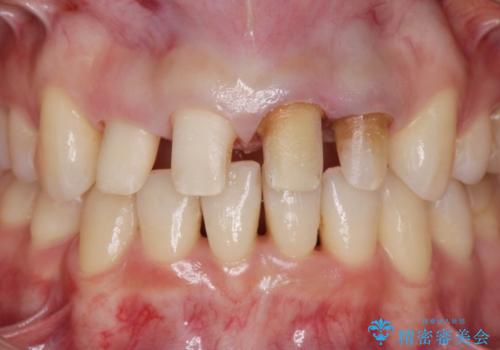

- 神経の死んでしまっている前歯の変色の改善を求めて来院されました。

根管治療をしたのち時間が経過して変色が目立つ歯と、レジン充填が複数箇所に及んでいる歯も同時にオールセラミック治療を行っていくこととなりました。